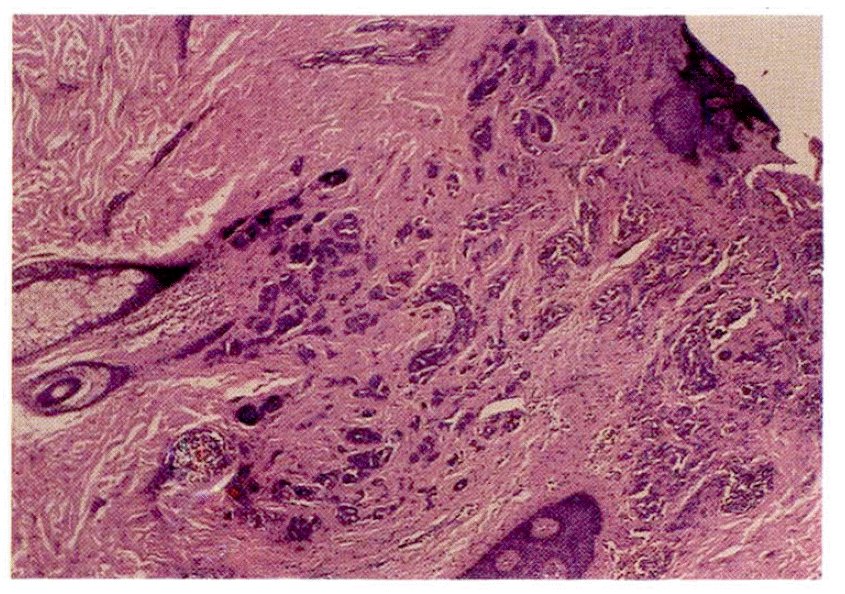

Fig. 5.

Tumor cells in the bronchoscopic biopsy specimen, revealing abundant pink granular cytoplasm and pleomorphic nuclei containing peripherally clumped chromatin and prominent nucleoli, which is the same histology as that of a previous specimen (Fig. 1) (HE, × 400)